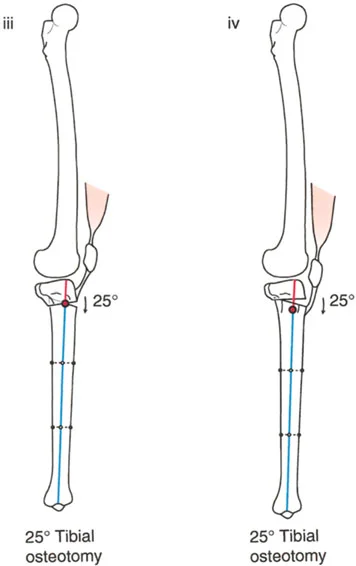

- زاوية الانحناء القريبة للظنبوب (PPTA - Proximal Posterior Tibial Angle): تقيس زاوية الجزء العلوي من عظم الساق. القيمة الطبيعية حوالي 80 درجة. الزيادة في هذه الزاوية (أكثر من 80 درجة) تشير إلى ارتداد ظنبوبي.

- مركز دوران الزاوية (CORA - Center of Rotation of Angulation): يتم تحديد هذا النقطة على الأشعة السينية لتحديد مكان التشوه العظمي بدقة، وهو أمر بالغ الأهمية لتخطيط عملية قطع العظم.

- الركبة الارتدادية بسبب الارتداد الظنبوبي:

- إذا كانت درجة فرط التمدد (HE) تساوي درجة الارتداد الظنبوبي (PPTA > 80°)، فهذا يعني أن التشوه كله ناتج عن عظم الساق.

- في هذه الحالة، يكون مركز CORA في الجزء القريب من عظم الساق.

2. العلاج الجراحي: قطع العظم (Osteotomy)

الهدف من جراحة قطع العظم هو إعادة محاذاة العظام وتصحيح التشوه الزاوي في المستوى السهمي، لاستعادة وظيفة الركبة الطبيعية واستقرارها.

أ. قطع العظم الفخذي لتصحيح الارتداد الفخذي:

- متى يتم إجراؤها: عندما يكون التشوه الرئيسي في عظم الفخذ البعيد.

- الإجراء: يتم إجراء قطع للعظم (عادة قطع عظم انثناء) في الجزء البعيد من عظم الفخذ، عند مركز دوران الزاوية (CORA)، لإعادة محاذاة العظم.

- الهدف: تصحيح فرط تمدد الركبة واستعادة المحاذاة الطبيعية.

- مثال: لتصحيح ارتداد فخذي بمقدار 20 درجة، يتم إجراء قطع عظم انثناء فخذي بمقدار 20 درجة.